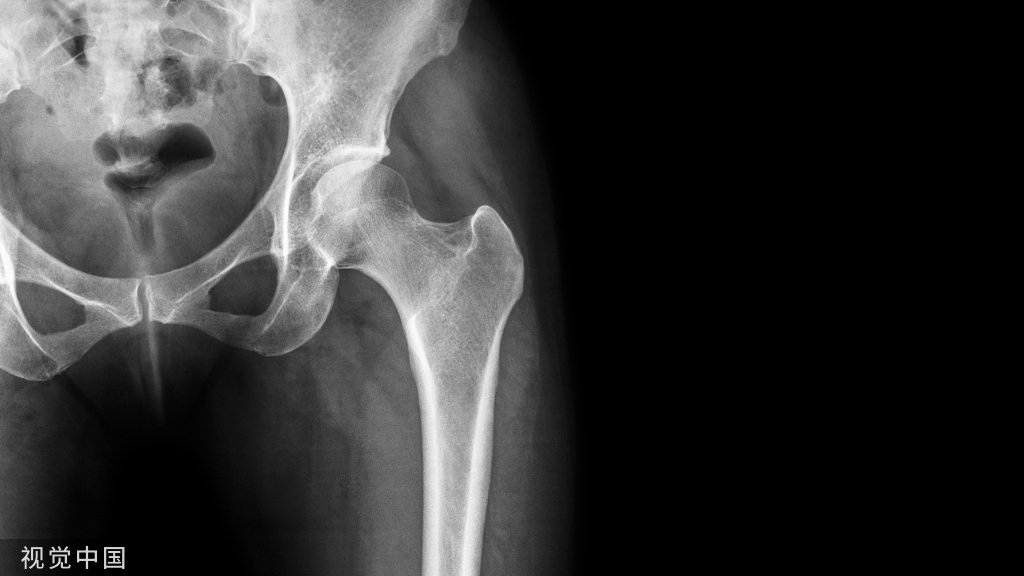

中:腰椎X片、CT、MR检查各有所用,相辅相成,不同检查,不同观察侧重,根据患者症状体征,选择一种或多种结合的检查手段,以便准确诊断。

(一)X线

X线片在判断脊柱骨结构及序列变化上较其他影像学方法有诸多优势,提示椎间盘突出方面的间接征象有局部不稳、椎间隙变窄、代偿性侧凸、牵张性骨赘等,但不能直接显示腰椎间盘突出,因此无直接诊断意义,不能作为诊断腰椎间盘突出症的方法(3级推荐)。

(二)CT

CT及三维重建方法可提高腰椎间盘突出症的检出率。CT较X线片可以更好地观察骨性结构,但对神经、椎间盘等软组织的分辨率较差,较难分辨椎间盘与神经根的关系(1级推荐)。

(三)MRI

MRI为腰椎间盘突出症首选的影像学检查手段。与CT相比具有以下优势:无放射性损害、可评估椎间盘退变情况、更好地观察突出椎间盘与神经根的关系,但对骨性结构压迫的分辨能力较低(1级推荐)。

美:1.目前并没有高质量的临床研究证明影像学诊断腰椎间盘突出神经根病的优势。工作组专家推荐有腰椎间盘突出神经根病病史和体检阳性结果的患者,MRI检查是最为合适的无创影像学检测手段。若患者行MRI检查存在禁忌,或者检测后无法判断结果,则推荐CT作为次选手段。证据等级:专家共识

2.对诊断腰椎间盘突出神经根病,并存在相对应病史和体检阳性结果的患者,推荐无创的MRI作为影像学检测的首选方法。推荐等级:A